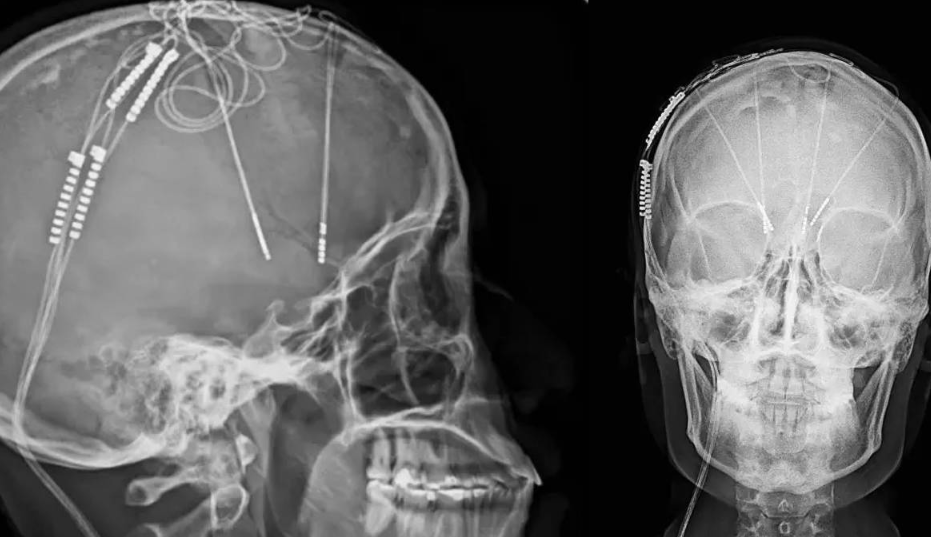

La intervención se llevó a cabo en el Hospital Internacional de Colombia, en Bucaramanga, el pasado 9 de abril, aunque recientemente fue revelada públicamente. La paciente, Lorena Rodríguez, de 34 años, sufría depresión resistente al tratamiento desde hace más de 17 años. Fue sometida a una cirugía de estimulación cerebral profunda, con el implante de cuatro electrodos en zonas específicas del cerebro mientras permanecía consciente.

Durante seis horas, el equipo médico liderado por el neurocirujano William Omar Contreras monitoreó en tiempo real las respuestas de la paciente. Se implantó un dispositivo similar a un marcapasos en el tórax, el cual emite impulsos eléctricos que ayudan a regular las conexiones neuronales alteradas.

El dispositivo implantado puede modular múltiples regiones cerebrales gracias a los cuatro electrodos, lo cual permite abordar una gama más amplia de síntomas, desde culpa obsesiva hasta ansiedad severa. A nivel global, apenas unas 400 personas han recibido este tipo de intervención, principalmente en Europa y Canadá. Este avance convierte a Colombia en pionera en América Latina.